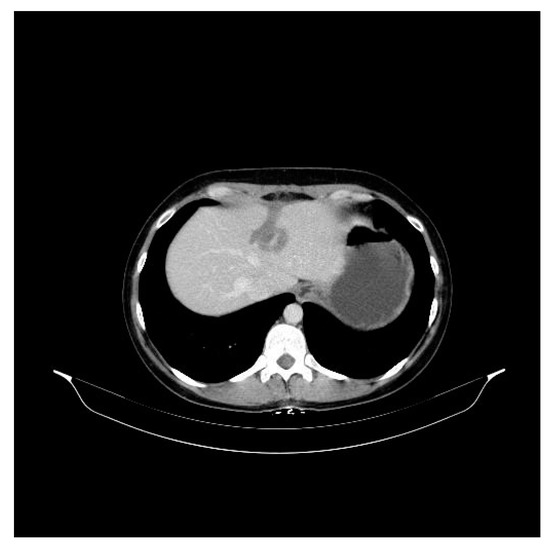

2. Case Presentation